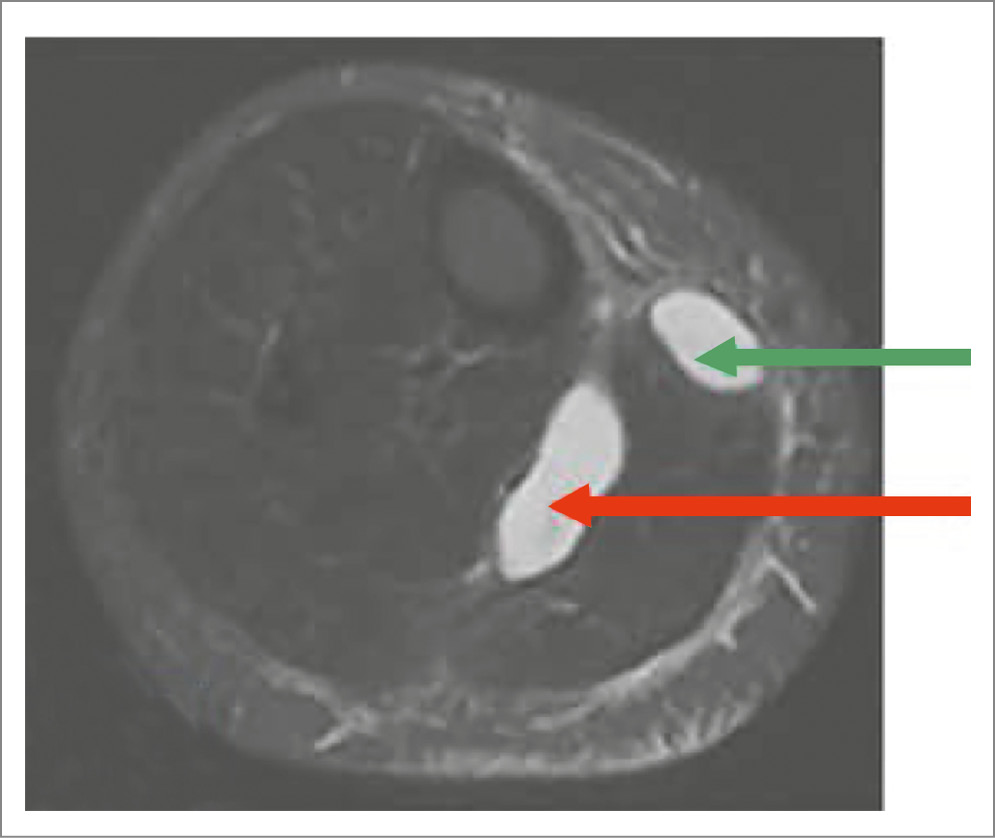

На МРТ разрыв КБ визуализируется как истечение жидкости в межмышечные пространства (рис. 3–5).

Рис. 3. МРТ голени, аксиальный срез, Т2-ВИ STIR. Разрыв КБ с истечением содержимого подкожно (зеленая стрелка) и межмышечно, сепарация медиальной головки икроножной мышцы (красная стрелка).